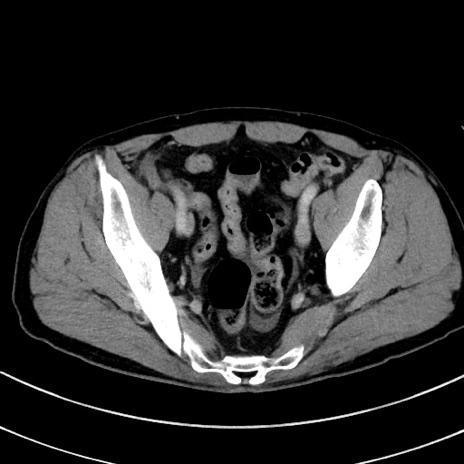

冠状断像

症例8(横断像)

【症例】 60歳代男性

【主訴】 黒色吐物

【現病歴】 4日前から嘔気自覚、2日前の朝食後にも嘔気あり、自分で手で嘔吐反射起こし嘔吐したところ血が混ざっていたため受診。

【既往歴】 5年前汎発性腹膜炎を伴う急性虫垂炎で手術、高血圧、前立腺肥大症、高脂血症

【身体所見】 腹部正中に手術癩痕あり 腹部平坦・軟圧痛なし膨満感あり

【データ】WBC 8400、CRP 4.54